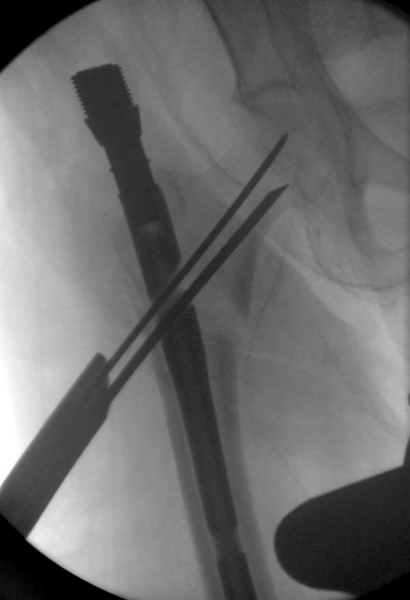

Мы получили испытательный вариант инструментария для пробы, хотя компания объявила, но ещё не для широкой публики, обещают к сентябрю. За полтора месяца, включая сегодняшнюю, вот уже восьмая операция по счету. Удобный инструментарий, ничего лишнего, научились делать быстро, посмотрим что будет, пока нравится.

Здесь сканнированные снимки импланта и операционные снимки больной.